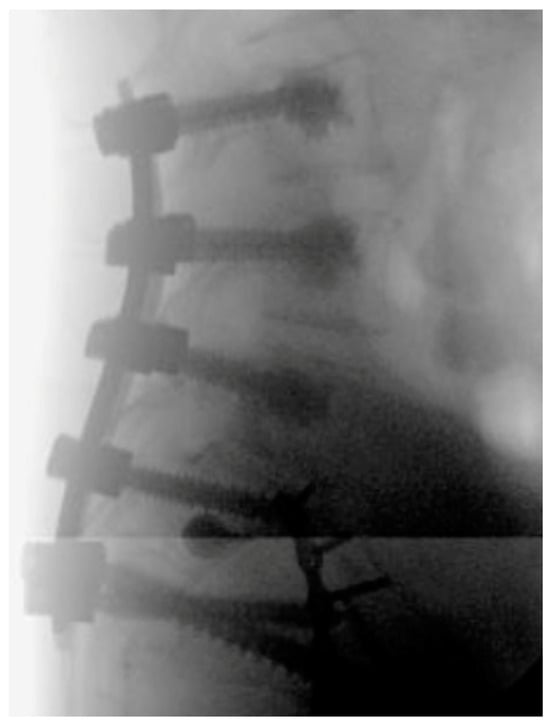

Minimally Invasive and Navigation-Assisted Fracture Stabilization Following Traumatic Spinopelvic Dissociation

4. Evolution of Open Surgery to Minimally Invasive Techniques for Lumbopelvic Fixation

5. Techniques and Considerations in Spinopelvic Fixation: Sequence, Reduction, and Avoiding Complications

6. Spinopelvic Fixation Percutaneous Technique